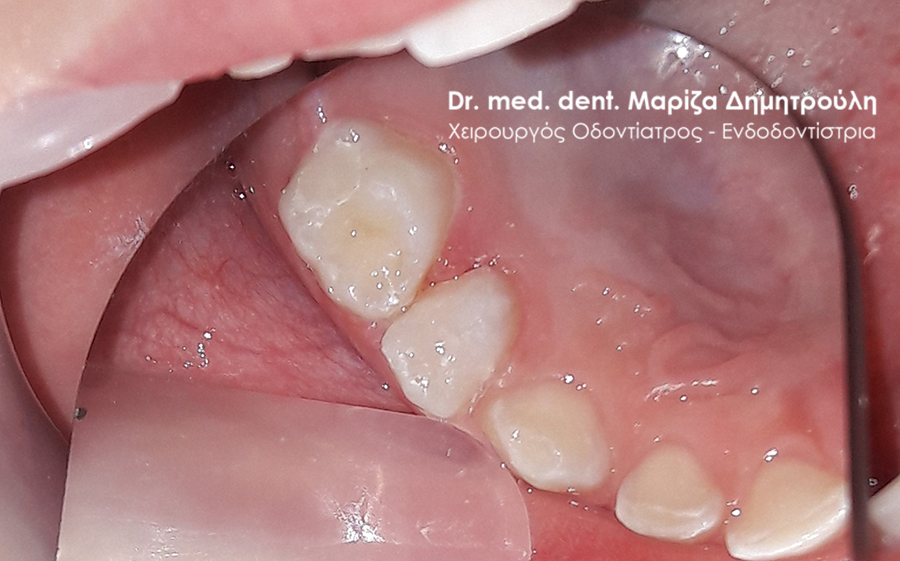

Dental filling of primary tooth

AFTER